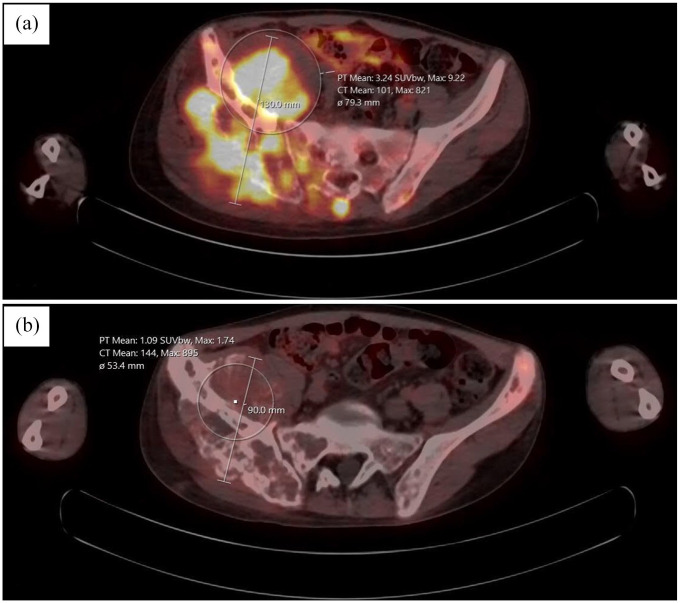

Case presentation: We present a case of 16-year-old patient with Ewing sarcoma diagnosed with neoplastic fever.